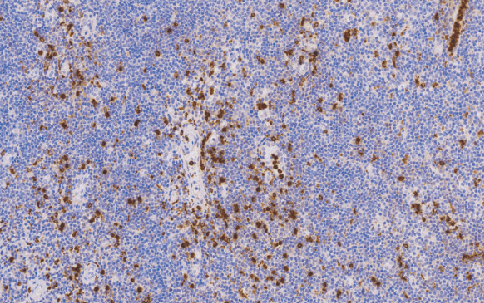

Lysozyme兔抗人溶菌酶多克隆抗体

溶茵酶是组织细胞及其肿瘤细胞的标记物,主要用于组织细胞瘤、恶性纤维组织细胞瘤、恶性组织细胞增生症和组织细胞性恶性淋巴瘤的诊断。及髓样细胞肿瘤和淋巴样细胞肿瘤的鉴别诊断。

- 阳性部位:胞质

- 适用组织:石蜡切片 /冰冻切片

- 预处理:热修复